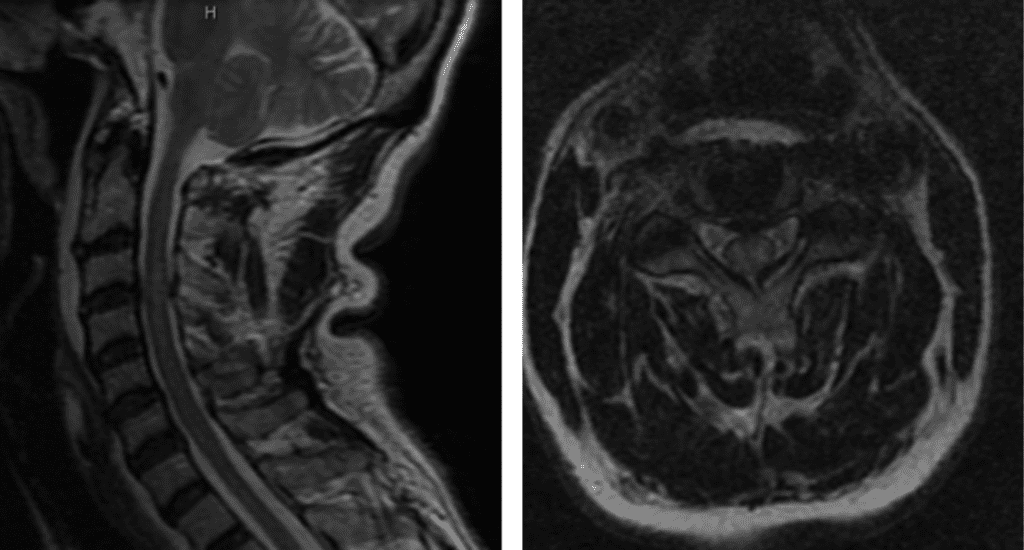

This patient was suffering from compression of the cervical spinal cord. The fall caused an acute herniation of the cervical disc, which caused pressure on the spinal cord.

Figure 1. T2 MRI sagittal and axial showing C3/C4 disc herniation with compression of the spinal cord; spinal cord edema at the C3/C4 level.

This particular spinal cord injury is called Central Cord Syndrome. This type of spinal cord injury typically affects the hands more than the legs and requires urgent surgical attention.